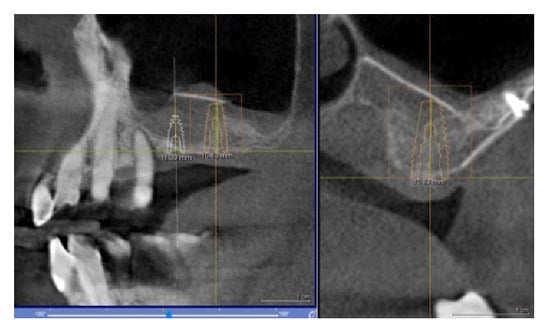

In this case, we observed how modern 3D reconstruction techniques can be a good support in regenerative surgery. In fact, starting from dicom files format, obtained with cone-beam computed tomography (CBCT) (Osteophoenix, Erandio-Vizcaya-Spain) it was possible to simulate “ex-ante” the surgical procedure. In addition to the reconstruction of the mandible (Figure 10a), the extraction of molars 4.6 and 4.7 was also simulated.

Figure 10.

(a) 3D model of the mandible; (b) Titanium foil digital design.

A titanium foil barrier was preventively designed and prepared in order to shorten surgical time (Figure 10b). In fact, the great advantage in cases like this is that the device does not need to be shaped during the surgical session.

The surgery protocol was the same as described in the previous case (Figure 11a–e). The extraction of teeth and the simultaneous insertion of the implants was performed in the same session (Figure 11a). The enriched clot (1 g beta-tricalcium phosphate for every 5 mL of clot) was protected by the shaped foil fixed with screws (Figure 11b) and its successive removal was at six months (Figure 11c). A further six months were necessary for soft tissue maturation (Figure 11d,e). In this case, the flap of keratinized mucosa, indicated by the white arrow in Figure 11c–e, contributed to the stability of the keratinized mucosa. At the follow-up, the gingival tissue was adequately matured, avoiding further graft of soft tissue (Figure 12).

Figure 11.

(a) Avulsion of the teeth and simultaneous insertion of the implants; (b) Use of the enriched clot and cover with the foil blocked with the screws; (c) Removal of the foil at six months; (d) Maturation of the tissues after one week from the withdrawal of the foil; (e) pre-prosthetic situation of implants and mucosa.